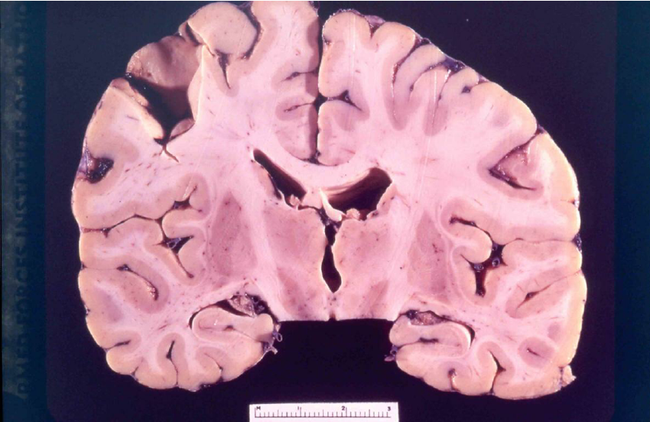

Tuy nhiên, y học ngày ấy lại không đủ khả năng để nhìn ra "thủ phạm" gây bệnh. Sau này khi các loại kính hiển vi hiện đại phát triển, các nhà khoa học đã tìm ra nguyên nhân chính là do prion – một cấu trúc vi sinh vật nhỏ hơn virus tới 100 lần. Đáng sợ hơn, chúng có khả năng chống lại tác động của môi trường và nhân bản rất nhanh, khiến người bệnh cứ vậy mà chết dần chết mòn trong tiếng cười.

Hiện tại không có phương pháp điều trị thành công cho bệnh Kuru, bởi những prion gây bệnh sinh sản rất nhanh và rất khó tiêu diệt. Theo chuyên trang sức khỏe Healthline, não bị nhiễm prion vẫn có khả năng lây nhiễm ngay cả khi được bảo quản kín sau nhiều năm.